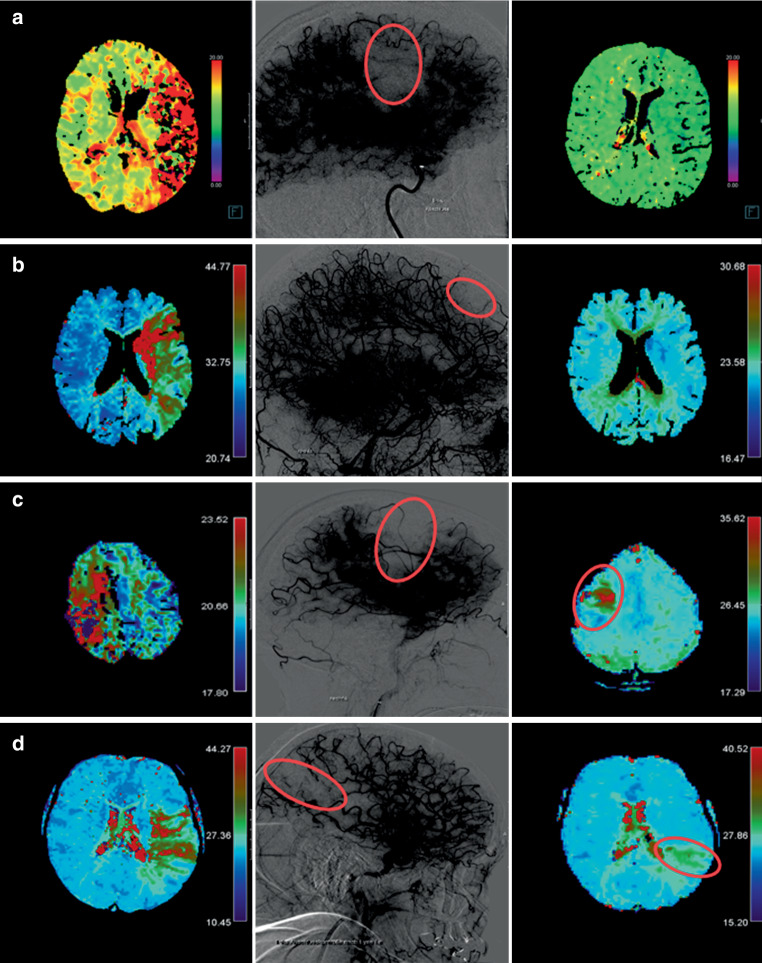

DR was the primary outcome of this study. It was defined as the absence of any focal perfusion deficit on time-sensitive maps of contrast-enhanced follow-up perfusion imaging (Fig. 1a,b). Conversely, persistent perfusion deficit (PPD) was defined as a persisting perfusion imaging deficit clearly visible on follow-up perfusion imaging (focally increased TTP and Tmax values on the ipsilateral, compared to the contralateral side), which corresponded to the location of the antegrade capillary phase deficit on the final angiography image of the incompletely perfused area after MT (Fig. 1c,d). Great care was taken to exclude false positive ratings of PPD caused by susceptibility artifacts/hemorrhagic transformations (Online Resources, Supplementary Figure 2). For this purpose, other sequences including SWI were assessed. Rating perfusion outcome as a dichotomized output was used with the aim of showing reliability of perfusion imaging outcome and its potential usefulness in future studies. Correspondingly, a qualitative approach offers simplified understanding of perfusion outcome for the readers and its practical use in clinical routine. Perfusion outcome was evaluated with centrally adjudicated charter distributed among the raters (Online Resources, Supplementary Methods 1). All qualitative ratings were performed by four neuroradiologists blinded to clinical data, with experience of > 20, > 15, > 5 and > 1 years. Interrater agreement was evaluated for a random sample of 50 patients.

Fig. 1.

Delayed reperfusion (DR) and persistent perfusion deficit (PPD) on perfusion follow-up imaging. Final angiography runs (middle panel) are displayed with high contrast in order to emphasize the capillary phase deficits. TTP and Tmax perfusion imaging maps were evaluated on admission (left panel) and follow up (right panel) examinations due to their high sensitivity rates (Olea Sphere v2.3; Olea Medical & syngo.via, Siemens). a Patient with a left side M1 occlusion with DR on CT follow-up after extended thrombolysis in cerebral infarction (eTICI) 2b50 reperfusion. b Patient with a left side ICA occlusion with DR on MRI follow-up after eTICI 2c reperfusion. c Patient with a right side M2 occlusion with PPD on MRI follow-up after eTICI 2b50 reperfusion. d Patient with a left side M1 occlusion with PPD on MRI follow-up after eTICI 2b50 reperfusion